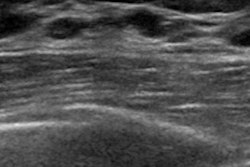

Scan of the liver of an obese patient. The image quality of the standard ultrasound probe (left) is significantly poorer than that of the high-performance probes (center and left). Image and caption courtesy of Universität Leipzig.